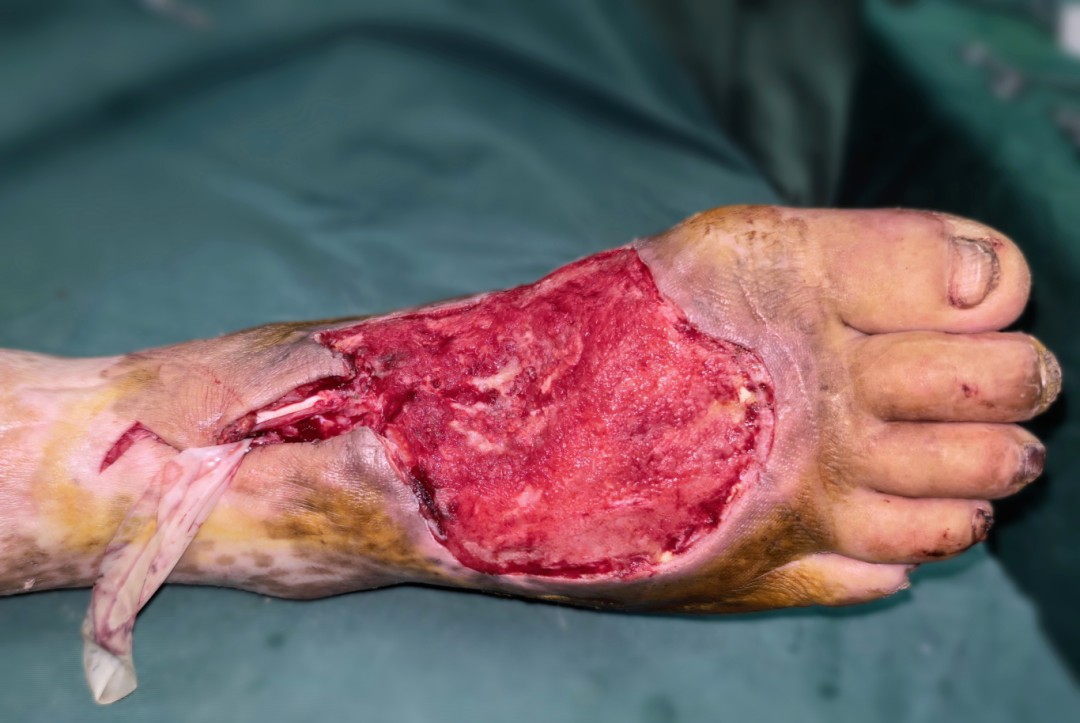

据悉,患者因复杂外伤导致足背大面积软组织缺损,创面情况复杂,若采用传统修复方式,难以有效修复,严重影响患者后续生活质量。面对这一棘手的诊疗难题,骨二科团队高度重视,联合铜仁市人民医院帮扶专家王宇茅进行多轮病例研讨。结合患者病情,专家团队最终确定采用选股外侧动脉降支穿支皮瓣(股前外侧皮瓣)游离移植修复方案,术中将股外侧皮神经与足背腓浅神经进行吻合,最大限度恢复患者足背皮瓣感觉功能。

术前创面情况